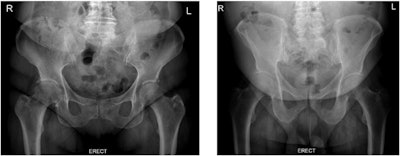

To address these challenges, the group tested whether radiation dose and image quality differ between two different erect pelvic radiographic procedures -- those with and without the displacement of anterior adipose tissue.

The radiographer who performed the exams properly positioned a thin cotton triangular bandage around patients, which they then held. Prior to the clinical study, the researchers had tested the material on an anthropomorphic phantom to ensure it would not be visible as an artifact.

"Image quality was generally better when patients had fat tissue displaced from the region of interest, as body part thickness decreased, resulting in improved contrast resolution and lower noise levels," the group wrote.